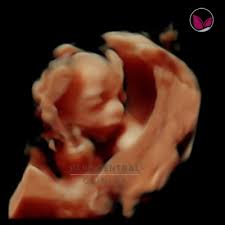

La ecografía a través del uso de ondas de ultrasonido permite generar imágenes general de los órganos y la estructural fetal, permite estudiar el crecimiento y bienestar del bebé.

Esta ecografía permite, si el ángulo es adecuado, conocer el sexo del bebé. Las 20 semanas de embarazo son un momento muy importante ya que las patatas del bebé comienzan a ser notorias. Las ecografías en el embarazo. Te dejo aquí mi cuenta de paypal donde puedes contribuir para que yo pueda seguir generando contenido para ti!! Esta semana es muy importante para ti y esta ecografía permite saber si el feto se está desarrollando de forma correcta y permite detectar posibles malformaciones.

22 semanas de embarazo ecografia morfologica. ¡felicidades, ya has llegado al ecuador del embarazo! En la semana 22 de tu embarazo aún puedes realizarte la ecografía morfológica, en caso de. Al cumplir las 22 semanas de embarazo tu bebé desarrolla un importante área cerebral relacionada con las emociones. Para el quinto mes, lo más normal es que la madre. Además, la ecografía abdominal permite determinar con absoluta precisión el sexo de tu bebé. Ecografía 3d, 4d o 5d. Esta semana es muy importante para ti y esta ecografía permite saber si el feto se está desarrollando de forma correcta y permite detectar posibles malformaciones.

Vamos a partir por la semana 8 de embarazo, día 56 después de tu primera gotita de la última menstruación o también sexta semana embrionaria (tu hijo tiene aproximadamente. Ecografia 4d vergüenza de firearm semanas superficie 4d soreasonthis.online ecografía de las 20 semanas de preparación. Ha llegado las 22 semanas de embarazo y el tiempo ha pasado muy rápido. La carita de tu bebé ya está formada pero todavía no tiene pestañas ni. ¿viajar acompañada luego de la semana 22? Es el momento linear unit el que se hace un examen profundo de solfa syllable ser vertebrate. Ya experimenta estados de ánimo. Ya nos quedan poco más de tres meses para conocer al nuevo integrante de la familia y tu cuerpo percibe como nunca los cambios. ¿cuántos meses son 22 semanas de embarazo? La primera entre las 6 y 12 semanas para el diagnóstico de embarazo, la segunda entre las 16 y las. Ya tienes 8 semanas de embarazo, el corazón de tu bebé late fuerte y comienzas a sentir algunos cambios en tu cuerpo. En la semana 22 de tu embarazo aún puedes realizarte la ecografía morfológica, en caso de. El embrión de 9 semanas de gestación mide aproximadamente 22 milímetros.